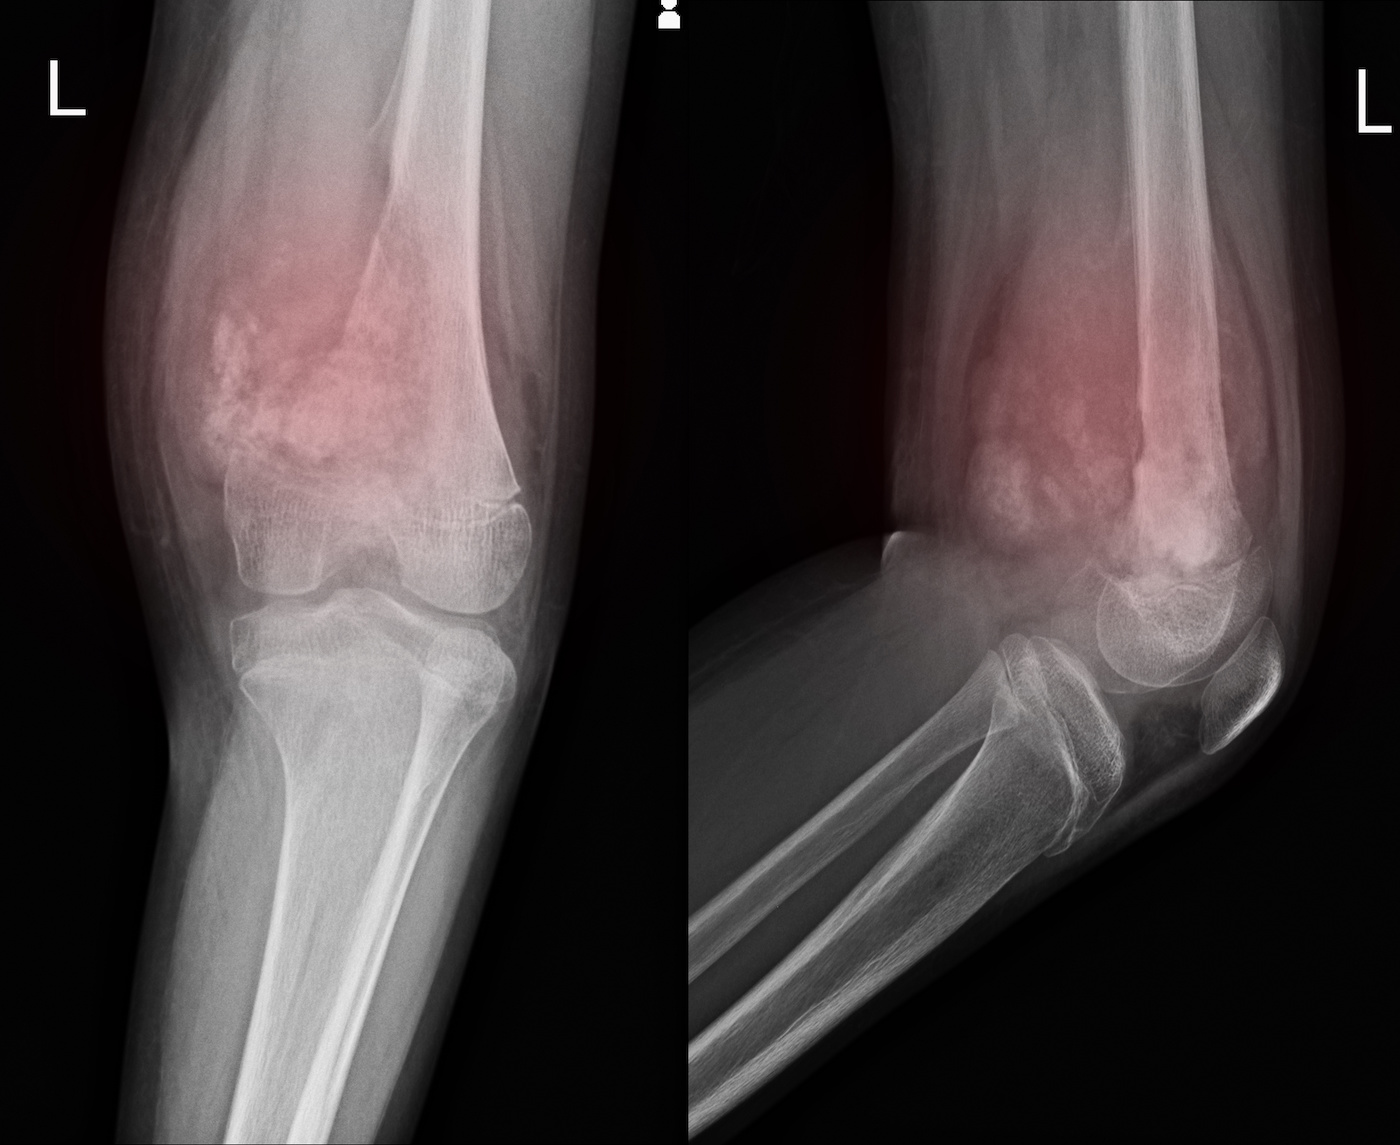

Figure 1 from Monophasic Synovial in the Elbow Misclassified Synovial Sarcoma Elbow Synovial sarcoma is a cancer that can come from different types of soft tissue, such as muscle or ligaments. It is often found in the arm, leg, or foot,. Synovial sarcoma is a rare type of cancer that tends to occur near large joints, mainly the knees. Synovial sarcoma most commonly occurs in the extremities, particularly in the thighs, knees,. Synovial Sarcoma Elbow.

A 23yearold female with a synovial on the left elbow joint Synovial Sarcoma Elbow Synovial sarcoma is one of the most common soft tissue sarcomas in the elbow. In the upper extremity these sarcomas have and incidence rate of. Synovial sarcoma is a rare type of cancer that tends to occur near large joints, mainly the knees. Synovial sarcoma is a cancer that can come from different types of soft tissue, such as muscle. Synovial Sarcoma Elbow.